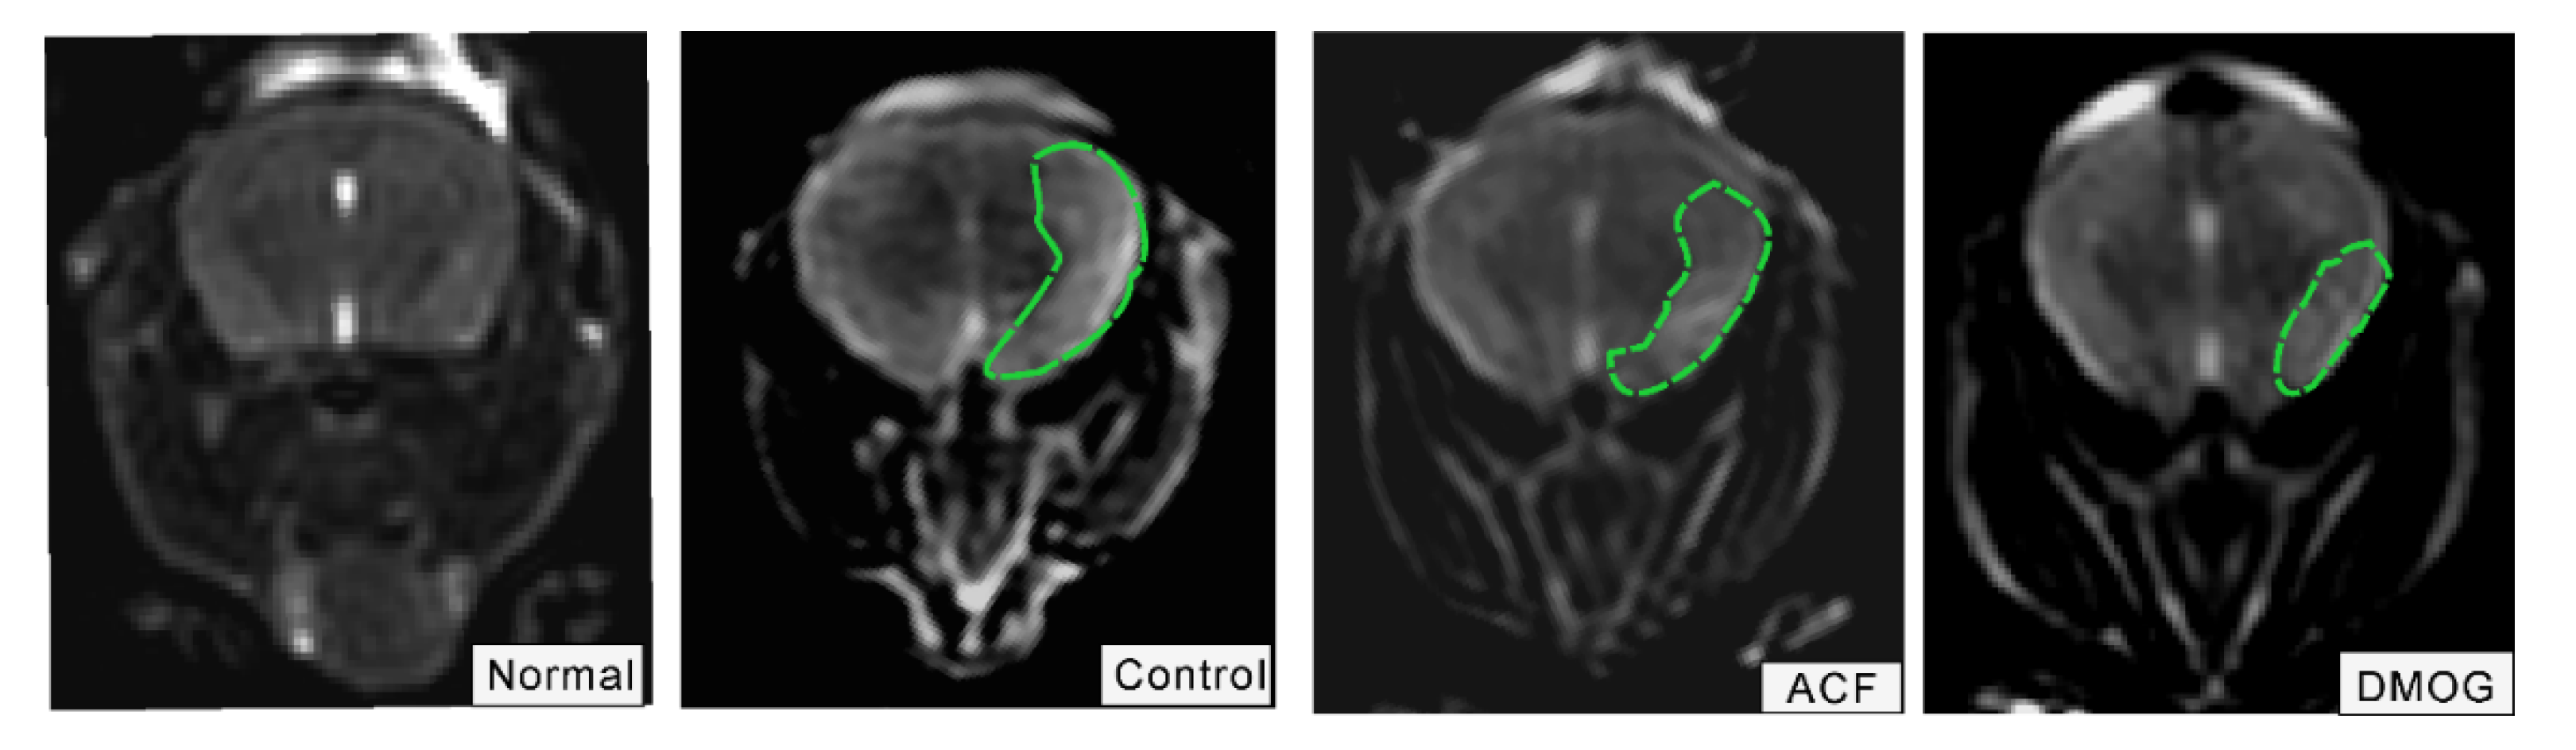

3.3. HIF-1α Activation Recovered the Brain Damage Following ET-1 Injection